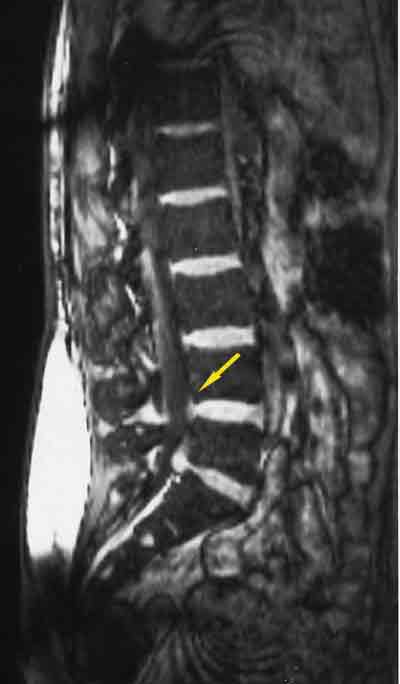

This patient has sciatica caused by disk herniation. Patients who present with sciatica have radicular symptoms more frequently than back pain. Because more than 95% of disk herniations occur at the L4-5 or L5-S1 level (arrow), the radicular pain typically extends below the knee. This radicular component helps differentiate true sciatica from nonsciatic conditions, such as trochanteric bursitis and hip osteoarthritis.

Image courtesy of David Della-Giustina, MD and Bradford A. Kilcline, MD.